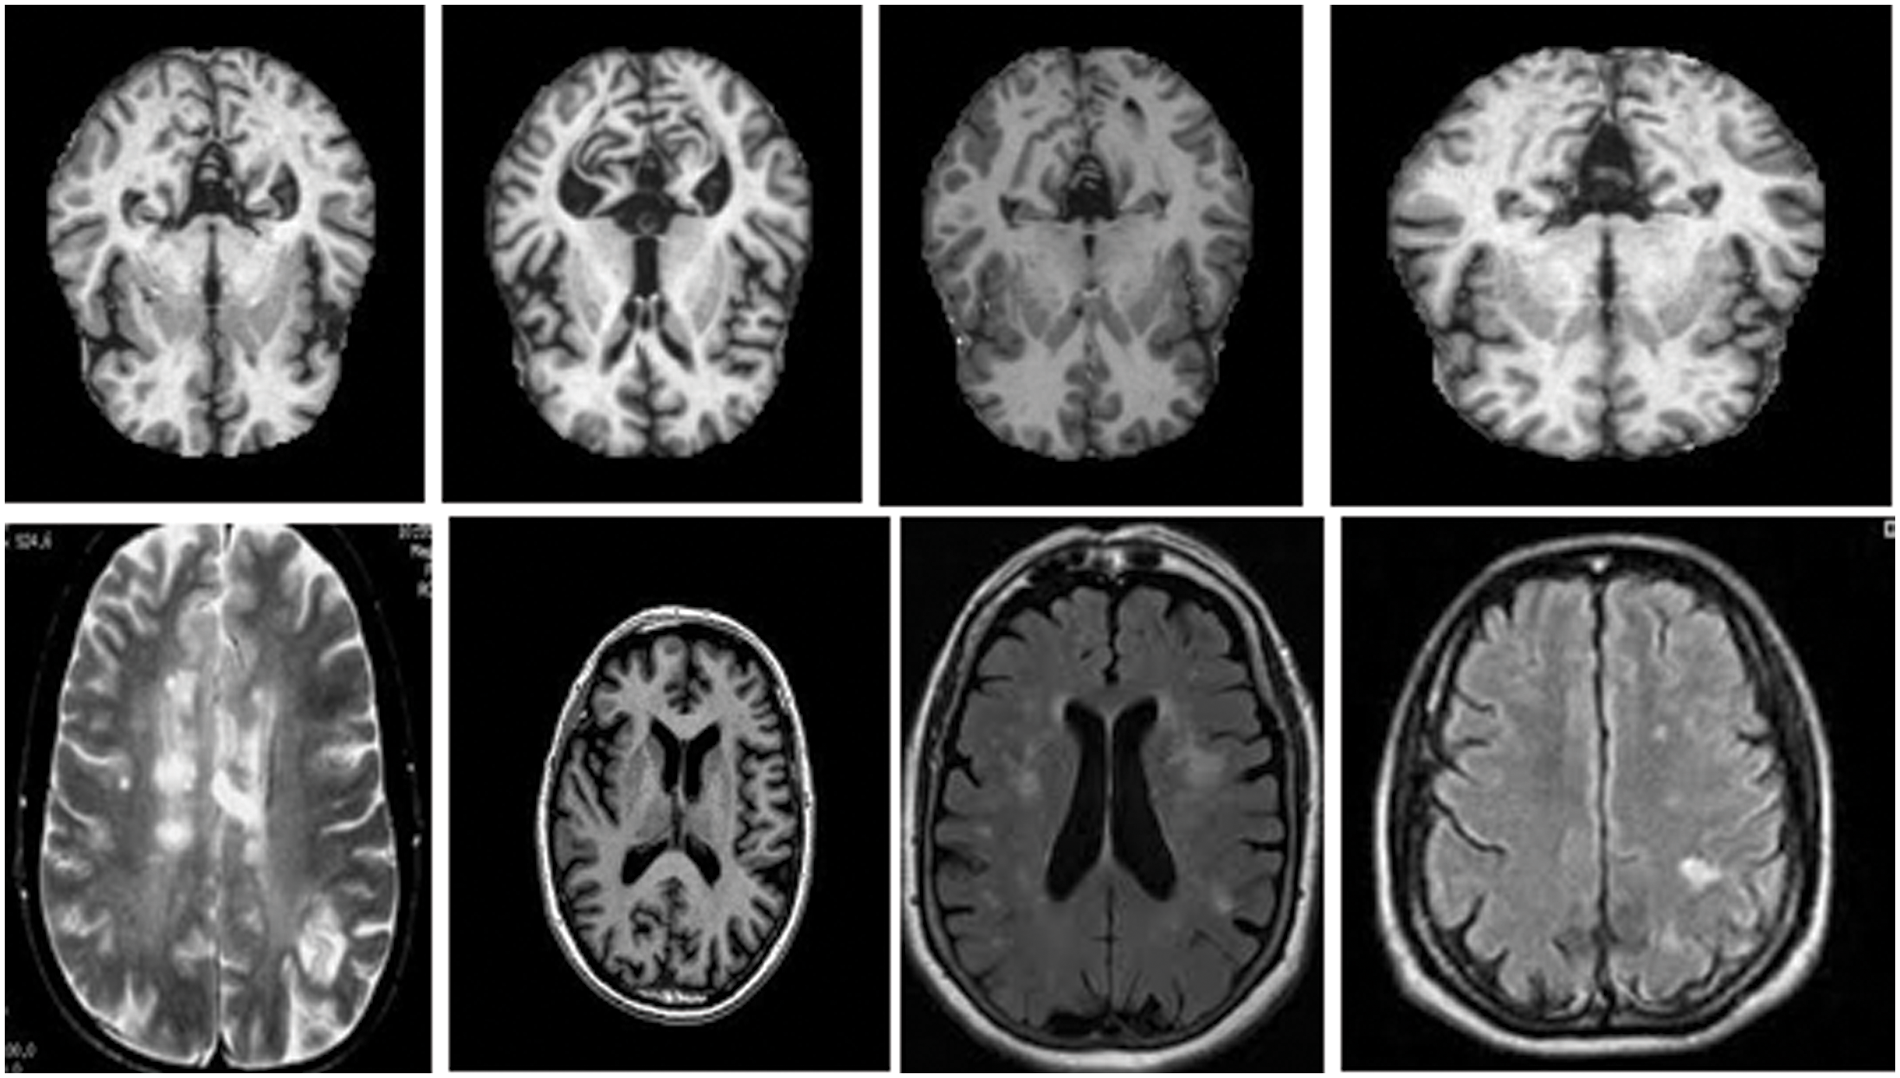

This section discusses the dataset collected from the Kaggle and the Harvard medical college website [27]. The total number of MRI images used was two thousand, with a distribution of five hundred for each category of normal images, images with brain stroke, Alzheimer’s disease brain tumour. These images are pre-processed with the skull removed and noise removed with median filters to improve the image quality. Fig. 5 shows the MRI images of normal, tumour, Alzheimer, and brain stroke under discussion.

Figure 5: Brain MRI Images [27]